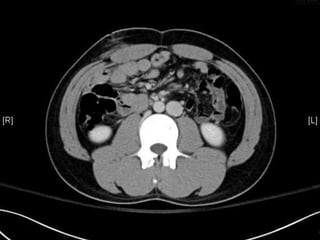

• CT:

 Shanmuganathan(2004)

 Sen:97%, spe:98%, accuracy:98% in penetrating stab wds

 Velmahos(2005)

 GSW: Sen 90.5, Spe: 96%

Radiology 2004:231:775-784

J trauma 2005:59:1155-1161